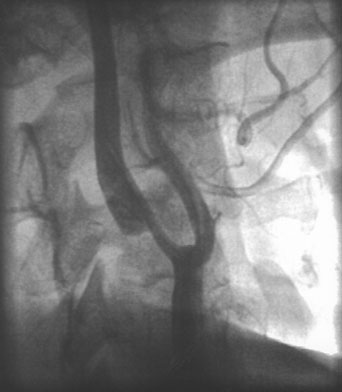

In the evaluation of extracranial large vessel disease, mainly carotid disease, ultrasound is the initial indicated study. It is commonly available, relatively inexpensive, and accurate. In addition, compared to other vascular imaging methods, it has the ability to directly image and characterize the plaque. Certain plaque characteristics may predict an increased risk of embolization. For example, the presence of an ulcer at the plaque surface may promote the formation of thrombus that can secondarily embolize, while a hypoechoic plaque, representing either intraplaque hemorrhage or a lipid-rich plaque, is associated with the potential for plaque destabilization.79,80 Carotid artery ultrasound has a sensitivity of 90% to 95% and specificity of 85% compared to catheter angiography.81 However, ultrasound may be unable to detect high-grade stenosis and mistakenly diagnose a carotid occlusion in 5% of cases. It is important to make this distinction as a patent vessel may be amenable to a revascularization procedure. Although power Doppler and echo-contrast agents may improve the odds of a correct diagnosis, for now it is standard practice to corroborate carotid occlusions with another imaging modality such as MRA, computed tomographic angiography (CTA), or conventional catheter angiography. MRA is an evolving technology comparable in accuracy to ultrasound, with the advantage of being able to image the distal carotid. In the past, there was a risk of overestimation of carotid stenosis by MRA, and beyond 70% stenosis, the absence of signal (flow gap) impeded adequate quantification of narrowing.82 Evolution in MRA technology and the use of contrast agents has improved the yield of this diagnostic method. Catheter angiography is the gold standard for carotid disease, but has inherent risks, with approximately 1% risk of stroke, although probably less in experienced centers. Figure 2 demonstrates the use of imaging technology in carotid disease.

Fig. 2. This 48-year-old diabetic man suddenly developed confusion and clumsiness of the right hand. On examination, he had inability to identify objects by touch and difficulty identifying the right from the left. A. Fluid attenuated inversion recovery (FLAIR) MRI shows a left parietal cortical infarct. Two potential embolic sources were noted: a left ventricular apical clot was seen on echocardiography from a presumed recent silent myocardial infarction, and ultrasound and subsequent angiography confirmed a significant left internal carotid stenosis. B: A 70% left internal carotid artery origin stenosis is shown on angiography. Monitoring both middle cerebral arteries with transcranial Doppler showed microembolic signals only over the left, suggesting that the carotid atherostenotic plaque was active or destabilized. C: An interruption (arrow) of the normal Doppler flow pattern of the middle cerebral artery is shown, representing a microembolic signal. The artery was stented rather than revascularized by endarterectomy because of the recent myocardial infarction. D: A patent revascularized carotid is revealed by ultrasound; note the struts of the stent.